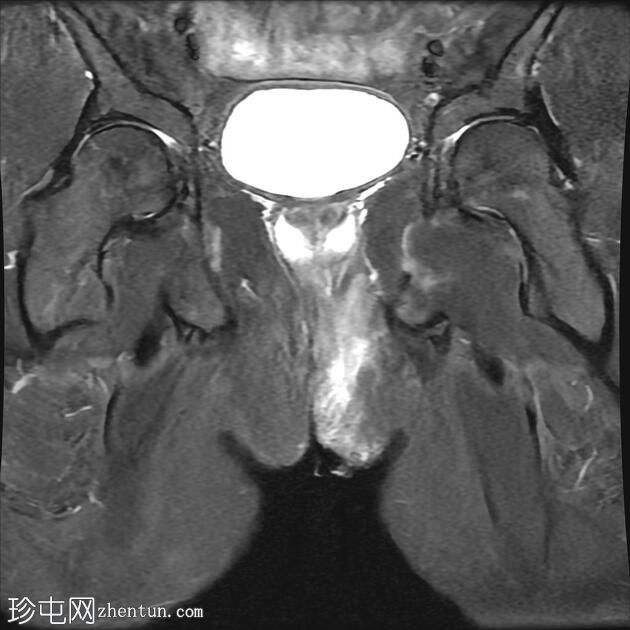

MRI

轴向位T2

脂肪饱和度

冠状位T1

一条68毫米厚的强化通道始于左侧肛周区域,向上穿过肛门内外括约肌,在2点钟方向开口于肛管。

无脓肿形成。

MRI成像特征与所述左侧经括约肌肛周瘘相符。